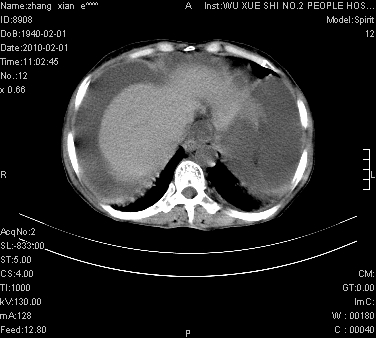

标题: CT24434:70岁 女 腹胀,腹水原因待查 [打印本页]

标题: CT24434:70岁 女 腹胀,腹水原因待查

大量腹水,脾脏囊性占位,子宫颈占位,右侧腹股沟淋巴结肿大,建议+c,先查妇科。

腹盆腔大量积液,子宫增大,子宫颈增大外形不规则,内见低密度影,膀胱后壁显示不清,右腹股沟肿大淋巴结,脾脏囊性占位,子宫颈占位,子宫颈癌?建议增强。

腹盆腔大量积液,子宫增大,子宫颈增大外形不规则,内见低密度影,膀胱后壁显示不清,右腹股沟肿大淋巴结,脾脏囊性占位,子宫颈占位,子宫颈癌?建议增强。支持!